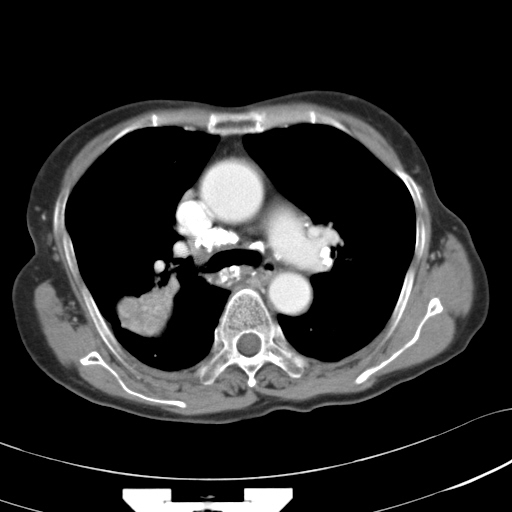

以下是引用hhcckk在2007-3-2 14:51:00的发言:[br]考虑结核球可能性大,依据[br]1病灶在下叶背段,结核的好发部位[br]2病灶内有大量的钙化,纵隔内有大量的淋巴结钙化[br]3重要的是半年前与现在相比无变化,假如是肿瘤的话不会这么‘善良’[br]4病灶周围卫星灶不明显,病灶有毛刺,胸膜凹陷,肿瘤不能完全排除,有条件的话最好做个活检

以下是引用liuyue在2007-3-2 17:15:00的发言:[br]1位置:右上叶后段[br]2性质:大分叶、粗长毛刺、条状斑片状钙化、纵隔多发淋巴结钙化,无强化,故考虑:肺结核灶(陈旧)